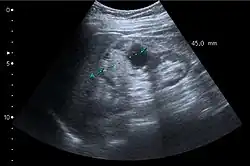

On renal ultrasonography, a solid renal mass appears in the US exam with internal echoes, without the well-defined, smooth walls seen in cysts, often with Doppler signal, and is frequently malignant or has a high malignant potential. The most common malignant renal parenchymal tumor is renal cell carcinoma (RCC), which accounts for 86% of the malignancies in the kidney. RCCs are typically isoechoic and peripherally located in the parenchyma, but can be both hypo- and hyper-echoic and are found centrally in medulla or sinus. The lesions can be multifocal and have cystic elements due to necrosis, calcifications and be multifocal (Figure 8 and Figure 9). RCC is associated with von Hippel–Lindau disease, and with tuberous sclerosis, and US has been recommended as a tool for assessment and follow-up of renal masses in these patients.[3]